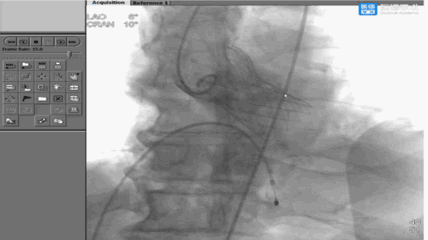

瓣膜释放后形态位置良好,造影微量返流

主动脉根部造影: